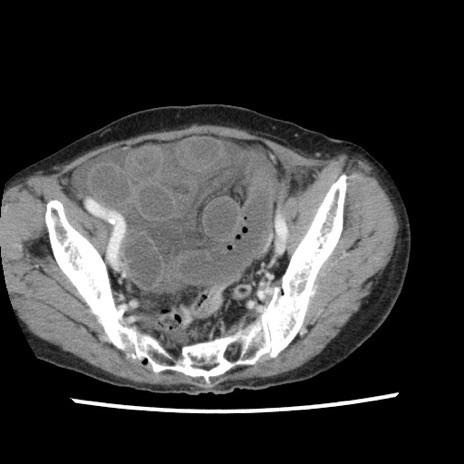

冠状断像

【症例】80歳代女性

【主訴】腹痛

【現病歴】8時間前から腹痛あり来院。

【既往歴】糖尿病、脂質異常症、子宮体癌にて子宮全摘術

【身体所見】意識清明・会話良好だが腹痛で苦悶様、全腹部にわたって反跳痛と圧痛あり

【データ】WBC 13600、CRP 0.14、LDH 224、CK 90